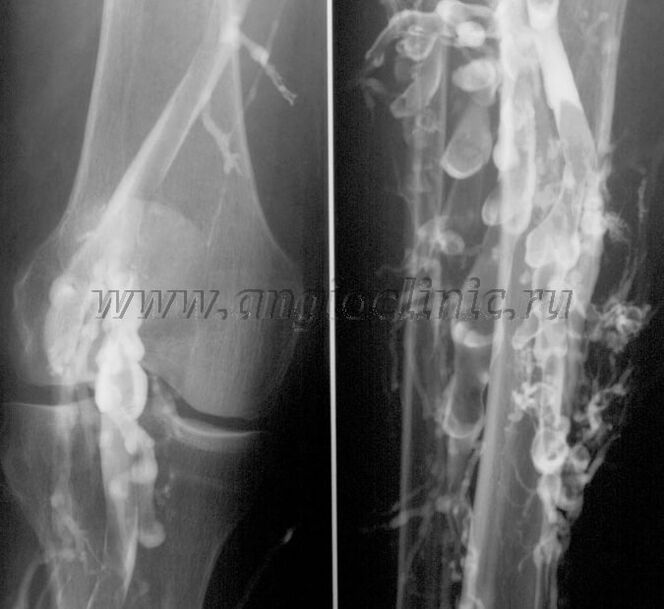

Contrast venography

Typically, ultrasound is sufficient for a complete diagnosis of venous pathology, but in some cases it is necessary to study the relationship between the state of the deep and superficial venous systems, especially in the case of recurrences of varicose veins and secondary varicose veins.

To resolve these problems, contrast X-ray examination is used.The saphenous veins are punctured and contrast is administered.The movement of the contrast is observed on the x-ray machine monitor, and all necessary tests and projections are performed.Currently, venography for varicose veins is used very rarely.